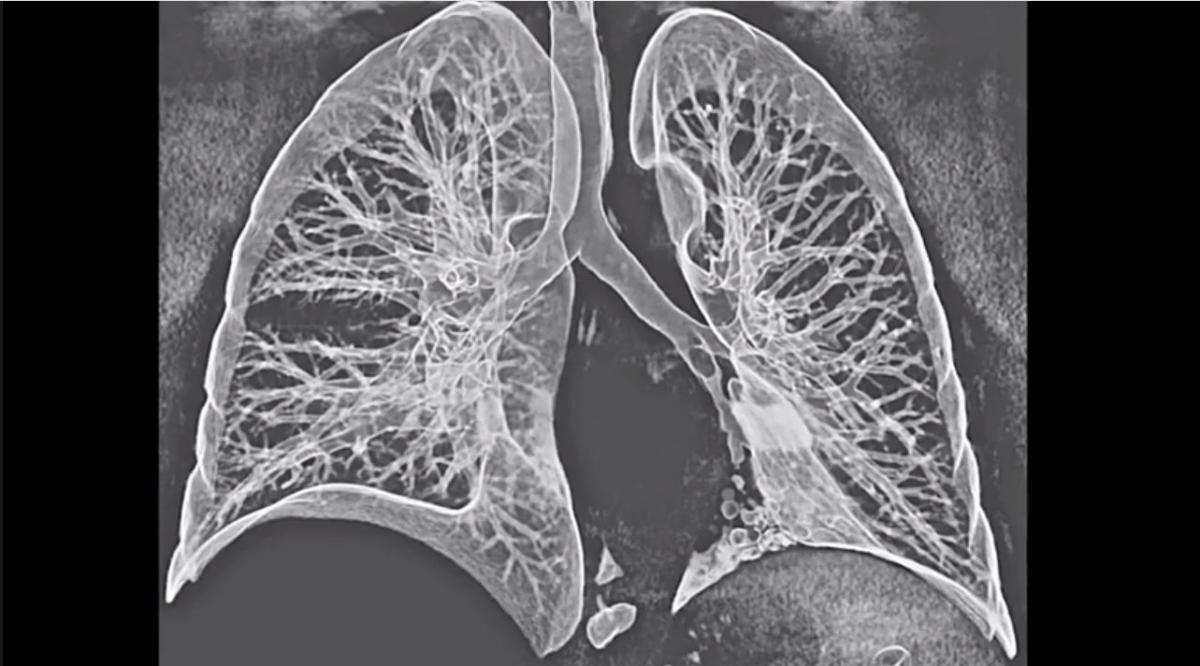

| Projected Outcomes Using Different Nodule Sizes to Define a Positive CT Lung Cancer Screening Examination David S. Gierada Paul Pinsky Hrudaya Nath Caroline Chiles Fenghai Duan Denise R. Aberle |